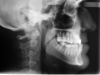

Fig 11. Pretreatment lateral (Fig 11) and posteroanterior (Fig 12) cephalometric x-rays, along with a lateral overjet image (Fig 13). Maxillary deficiency was present in the transverse and sagittal planes.

Figure 11